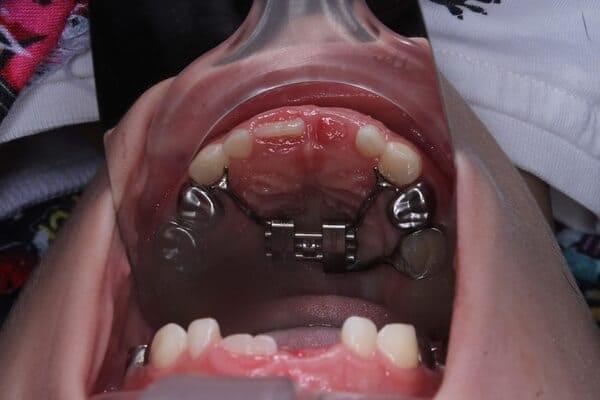

Дівчинка 4,5 років скаржилась на біль в нижньому зубі справа. В зв’язку з високою складністю процедур і значним об’ємом лікування (8 зубів) та після невдалої спроби лікування в звичайному режимі було прийнято рішення про лікування в умовах анестезіологічного забезпечення. Видаленно запалену пульпу (“нерв”) та проведено лікування каналів нижнього зуба ліворуч, цей та сусідні зуби покриті металевими коронками через значний об’єм ураження. Проліковані всі зуби, які потребували допомоги, щоб в майбутньому уникнути болю, дискомфорту та поширення інфекції. Через три години лікування дівчинка може комфортно жувати і не відчувати болю і дискомфорту.